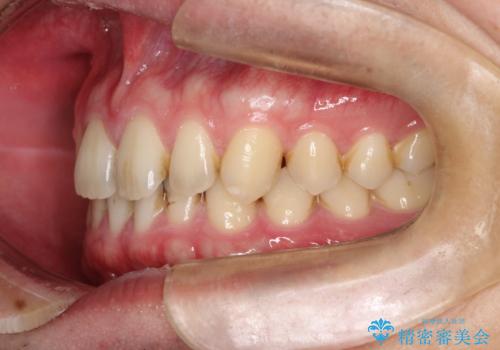

【インビザライン】前歯の隙間を治したい。

- 前歯の隙間を主訴に来院されました。

インビザラインにて治療しました。

ディープバイトも改善でき患者さんも満足されていました。

前歯の隙間だけを閉じる治療を行うだけでは、噛み合わせが悪くなるためディープバイトも改善が必要です。